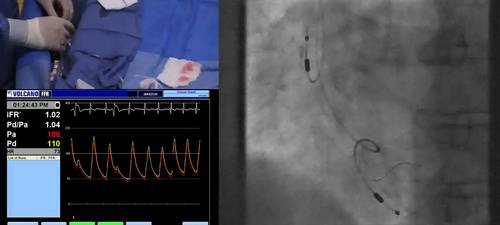

Dr Davies shows us how to advance the Verrata wire distally in the coronary artery, prior to making physiological measurements. Care is paid to the position of the guiding catheter and the position of the wire distally, as well as how to prepare to make a recording